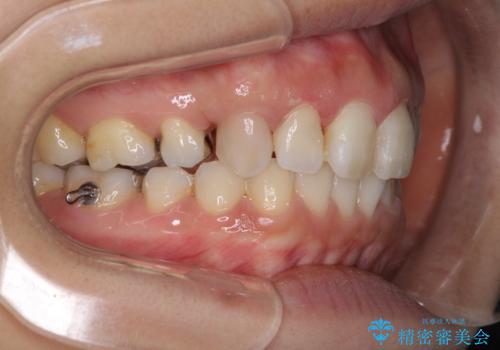

前歯の突出を軽減 インビザラインによる抜歯矯正

- 上の前歯の捻じれと突出感を気にして来院された患者様です。

目立たない装置を希望とのことで、上顎左右第一小臼歯を抜歯し、インビザラインにて矯正治療を行うこととしました。

インビザラインにて抜歯矯正を行うと、高頻度で奥歯が咬み合わなくなります。

抜歯スペースが閉じてからも咬みにくさ改善のためマウスピース矯正を継続するため、治療期間は長期化します。